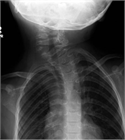

1. 乳児期に認められる頚部腫瘤が、エコー上胸鎖乳突筋の腫脹として捉えられ、正常の筋に認められる層状の筋内部エコー像に乱れが生じている場合には、筋性斜頚と診断する。

1. 一般に筋性斜頚は乳児期に診断されるが、その時期に診断されずに年長で斜頚位を呈している場合には、ときとして診断に難渋することがある。こういった場合には、胸鎖乳突筋の拘縮を触知できない場合でもエコー像では左右差を認めることが多く、診断に有用である。